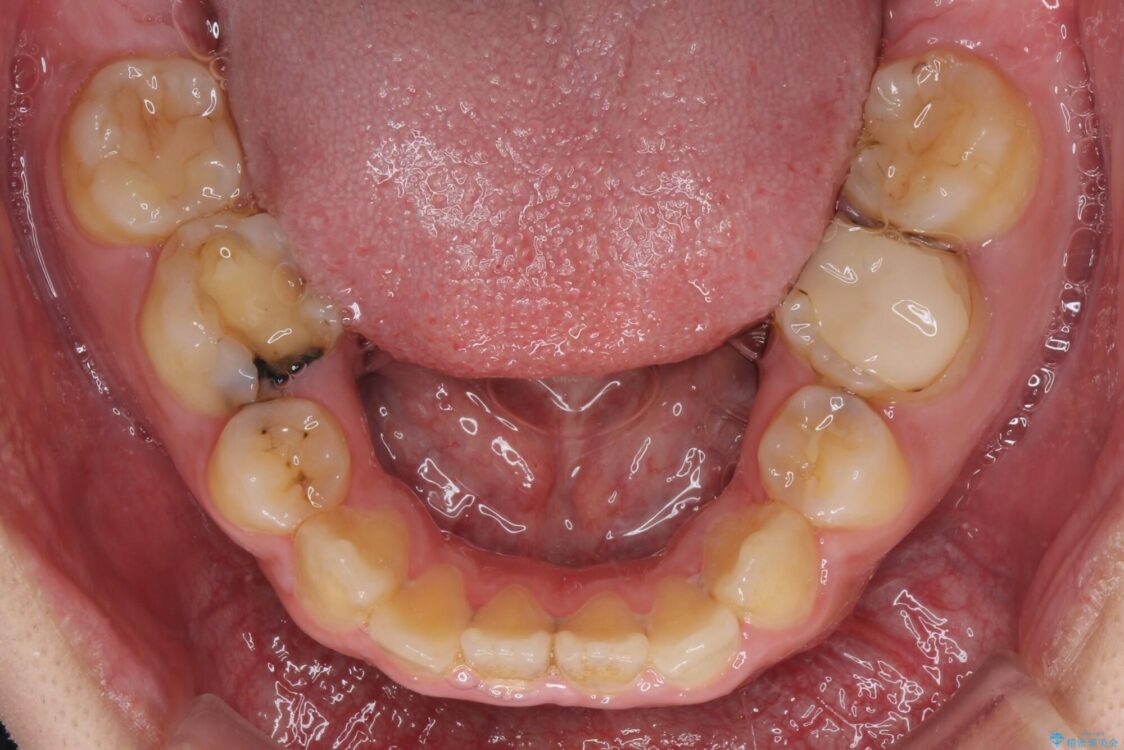

治療前

• 後戻りでデコボコの前歯 インビザライン矯正治療 治療前画像

高校時代に行った抜歯矯正が後戻りをしたとのことで来院された患者様です。

治療計画

再矯正であることから、目立ちにくい装置を希望されたため、インビザラインにて矯正治療を行うこととしました。

治療後について

下顎骨が左側に変位しているため、正中が合わないことは予想できましたが、歯列が整った後も咬み合わせが安定せず、咬み合わせを落ち着かせるために1年以上の期間を要しました。

噛みにくさの改善に時間がかかってしまうことがインビザラインの欠点の1つといえます。